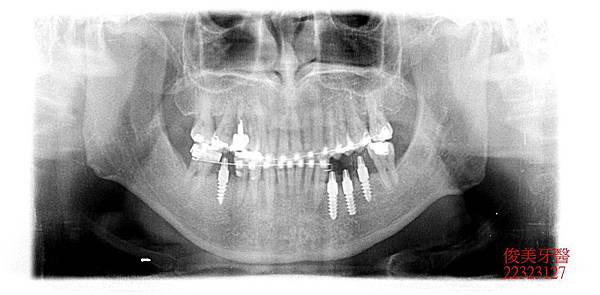

缺牙區皆在後牙咀嚼重力區,因此皆以植牙做修復,以支持整個咬合力量,減輕前牙的受力。

外觀暴牙幅度已縮小改善,臉型較為放鬆,肌肉不緊蹦。